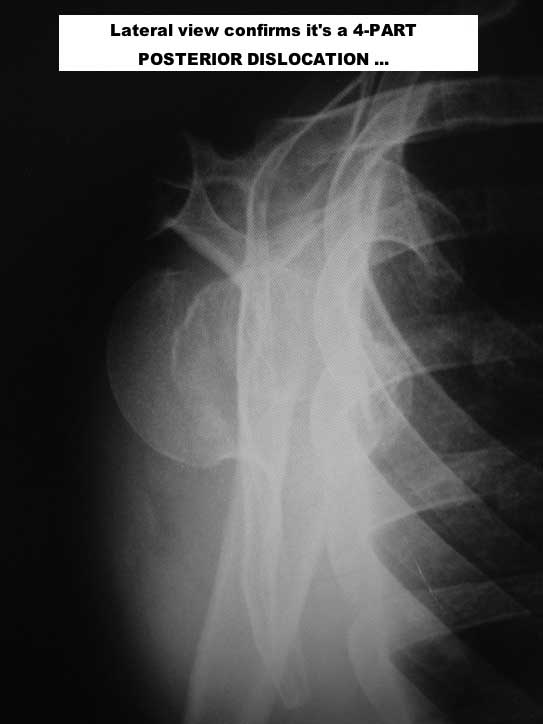

Here are some photos, of chronic, locked, 4 part posterior dislocation, 2 months old, that I did September/2011. Patient is 67, very, very active - had a really reasonable, honest clinical result ...

Photos attached ...